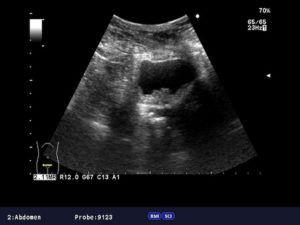

Дополнительными методами исследования выступают УЗИ, рентгенография, сцинтиграфия, МРТ и КТ и прочие.

Диагностика патологии начинается со сбора анамнеза пациента и гинекологического осмотра при помощи зеркал.

В этом случае врач может обнаружить новообразование, установить его форму и вид, выявить язвы, которые появились в результате распада новообразования. Затем исследуется подвижность матки, стенки влагалища, мочевой пузырь и прямую кишку.

Дальше врач назначает анализа крови, исследование мазка, проводит кольпоскопию и бимануальное исследование влагалища.

Главным методом диагностирования выступает биопсия, что дает возможность выявить стадию рака, строение и размер опухоли, а также спрогнозировать эффективность лечения. Также необходимо сдать кровь на онкомаркеры.